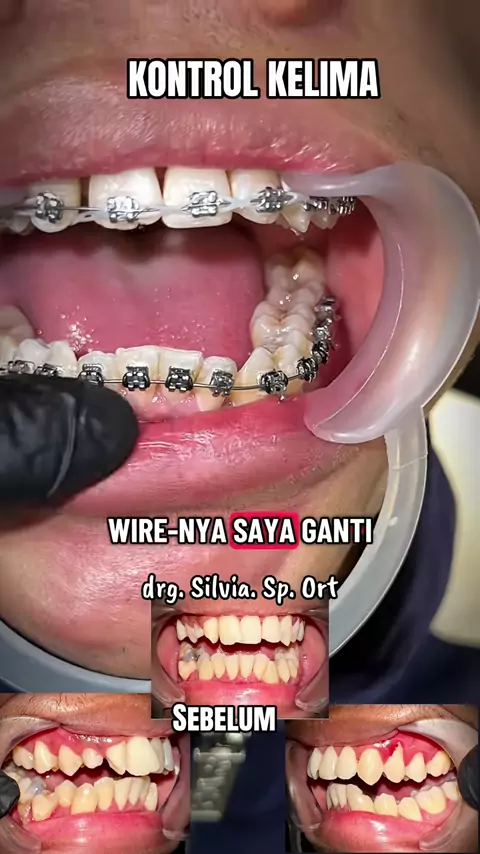

Risk it All... Risk all the cases Brain training Thinking Put it on Move it slowly With my mind and heart Still 3 times Need more but wish not that long Ambil Risiko Semuanya... Ambil risiko semua kasus Latihan otak Berpikir Insersi Gerakkan perlahan Dengan pikiran dan hatiku Masih 3 kali Butuh lebih banyak tapi berharap tidak lama lama I Wish I Pray Good night 🌹 Swet Dream drg. Silvia. Sp. Ort#behel#behelgigi#progress#orthodontist#

HARI INI (Kontrol Ke 4 ) Maloklusi kelas 1, gigi atas dan bawah berdesakan. Pergerakan pelan pelan saja dan semakin indah dalam 5 bulan, tidak terlalu lama. Masih perlu beberapa perawatan, tetapi kemajuannya nyata, perlu menemukan kunci oklusi di bagian posterior kanan. Rotasi gigi dan gigi yang berdesakan telah terkoreksi dengan baik. Alhamdulillah Y Rabb Semua ini karena tuntunanmu semata di pikiran dan hatiku, selama seluruh perawatan dan perjalanan pemasangan behel. Allah Maha Besar, Mah...